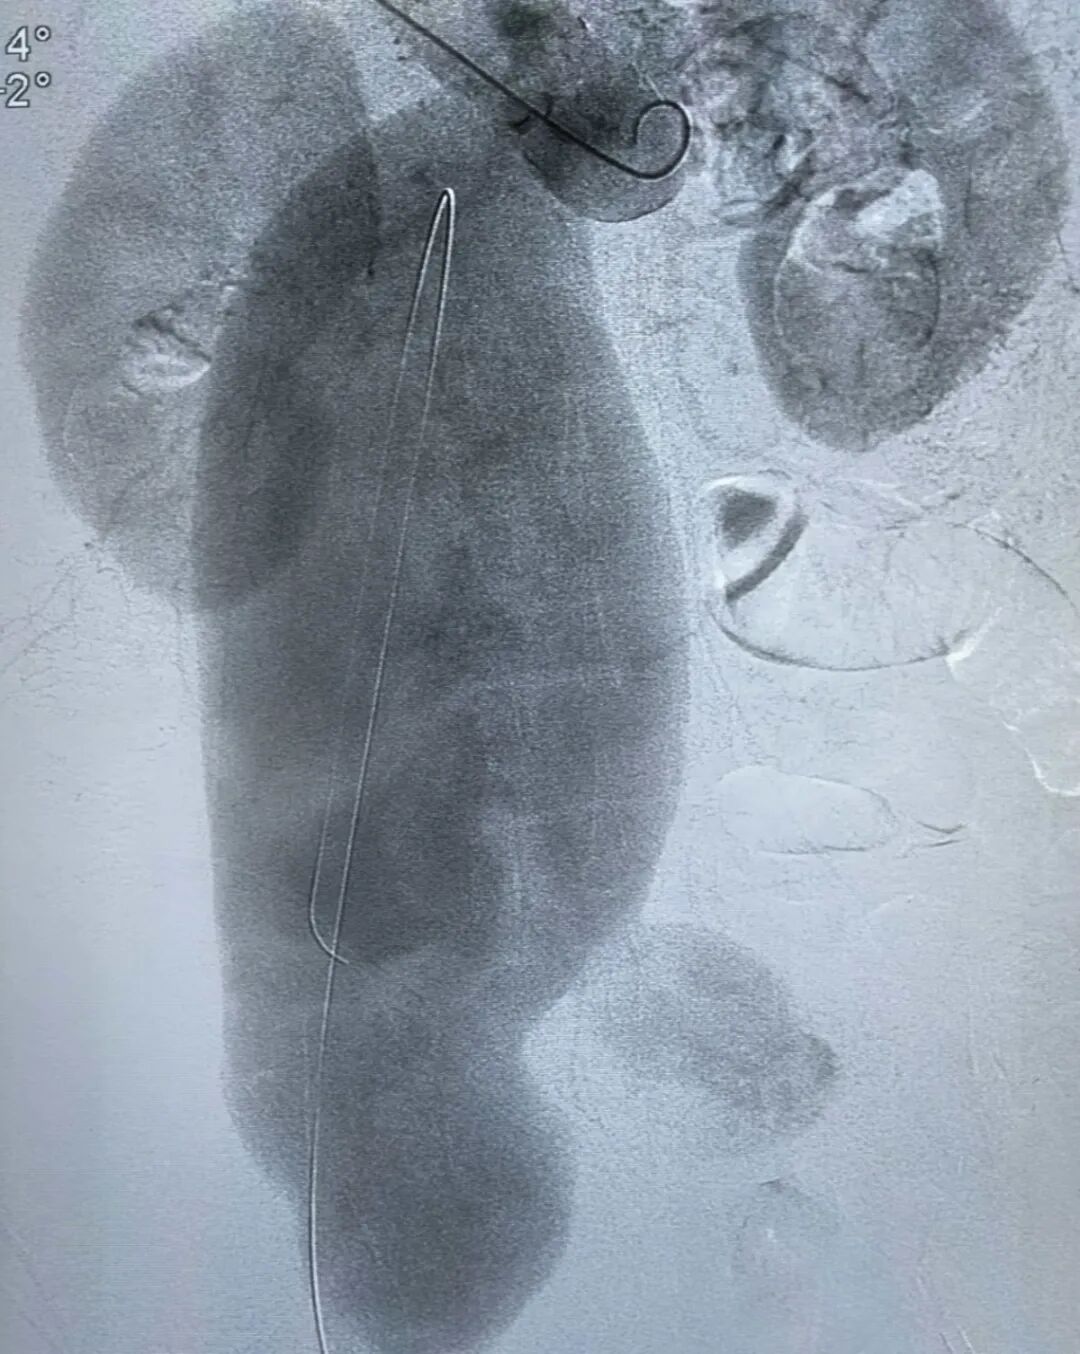

术前术后造影对比

手术过程中,在DSA影像设备的精准引导下,张永臻医师团队默契配合、操作娴熟,小心翼翼地操控导丝与支架,逐步穿越扭曲且严重钙化的血管段,最终成功将支架精准释放并固定于病灶部位。术后即时造影显示,支架位置理想,动脉瘤被完全隔绝,腹主动脉、双肾动脉及双髂内动脉血流通畅,无任何内漏情况,手术达到预期效果。